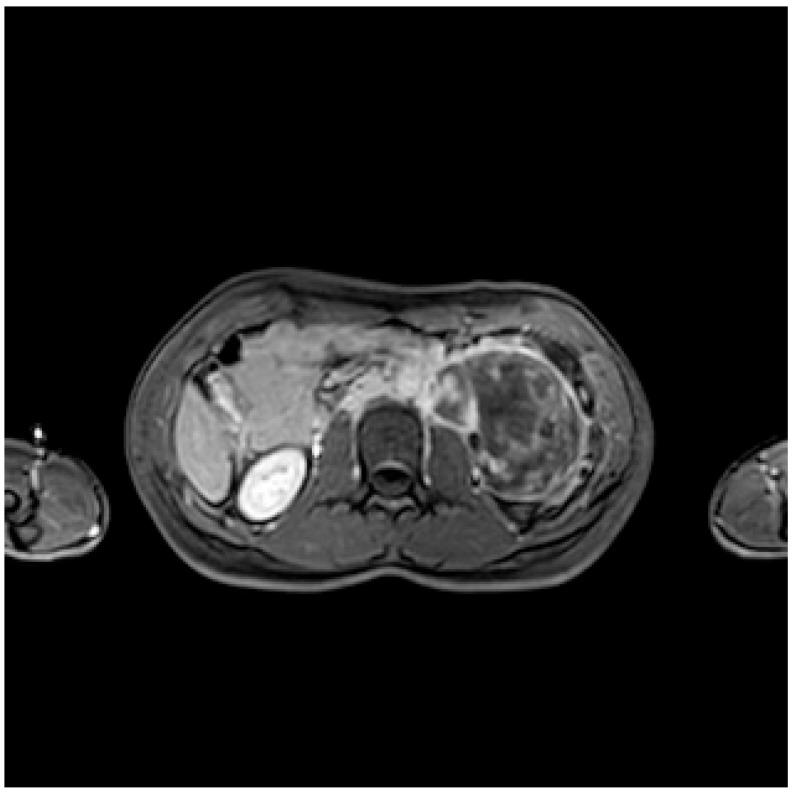

Retroperitoneal ganglioneuroma is a rare neuroectodermal tumor with a benign nature. We performed a literature review among 338 studies. We included 9 studies, whose patients underwent CT and/or MRI to characterize a retroperitoneal mass, which was confirmed to be a ganglioneuroma by histologic exam. The most common features of ganglioneuroma are considered to be a solid nature, oval/lobulated shape, and regular margins. The ganglioneuroma shows a progressive late enhancement on CT. On MRI it appears as a hypointense mass in T1W images and with a heterogeneous high-intensity in T2W. The MRI-"whorled sign" is described in the reviewed studies in about 80% of patients. The MRI characterization of a primitive retroperitoneal cystic mass should not exclude a cystic evolution from solid masses, and in the case of paravertebral location, the differential diagnosis algorithm should include the hypothesis of ganglioneuroma. In our case, the MRI features could have oriented towards a neurogenic nature, however, the predominantly cystic-fluid aspect and the considerable longitudinal non-invasive extension between retroperitoneal structures, misled us to a lymphatic malformation. In the literature, it is reported that the cystic presentation can be due to a degeneration of a well-known solid form while maintaining a benign character: the distinguishing malignity character is the revelation of immature cells on histological examination.

腹膜后神经节细胞瘤是一种罕见的良性神经外胚层肿瘤。我们对338项研究进行了文献综述。我们纳入了9项研究,这些研究中的患者接受了CT和/或MRI检查以对腹膜后肿块进行特征性描述,该肿块经组织学检查证实为神经节细胞瘤。神经节细胞瘤最常见的特征被认为是实性、椭圆形/分叶状以及边界规则。神经节细胞瘤在CT上表现为渐进性延迟强化。在MRI上,它在T1加权图像上表现为低信号肿块,在T2加权图像上表现为不均匀高信号。在综述的研究中,约80%的患者描述有MRI“漩涡征”。原始腹膜后囊性肿块的MRI特征不应排除实性肿块的囊性演变,并且在椎旁位置的情况下,鉴别诊断算法应包括神经节细胞瘤的可能性。在我们的病例中,MRI特征可能提示为神经源性性质,然而,主要为囊液成分以及腹膜后结构之间相当大的纵向无侵袭性延伸,使我们误诊为淋巴管畸形。在文献中,据报道囊性表现可能是由于已知实性形式的退变同时保持良性特征:区分恶性特征是组织学检查中出现未成熟细胞。